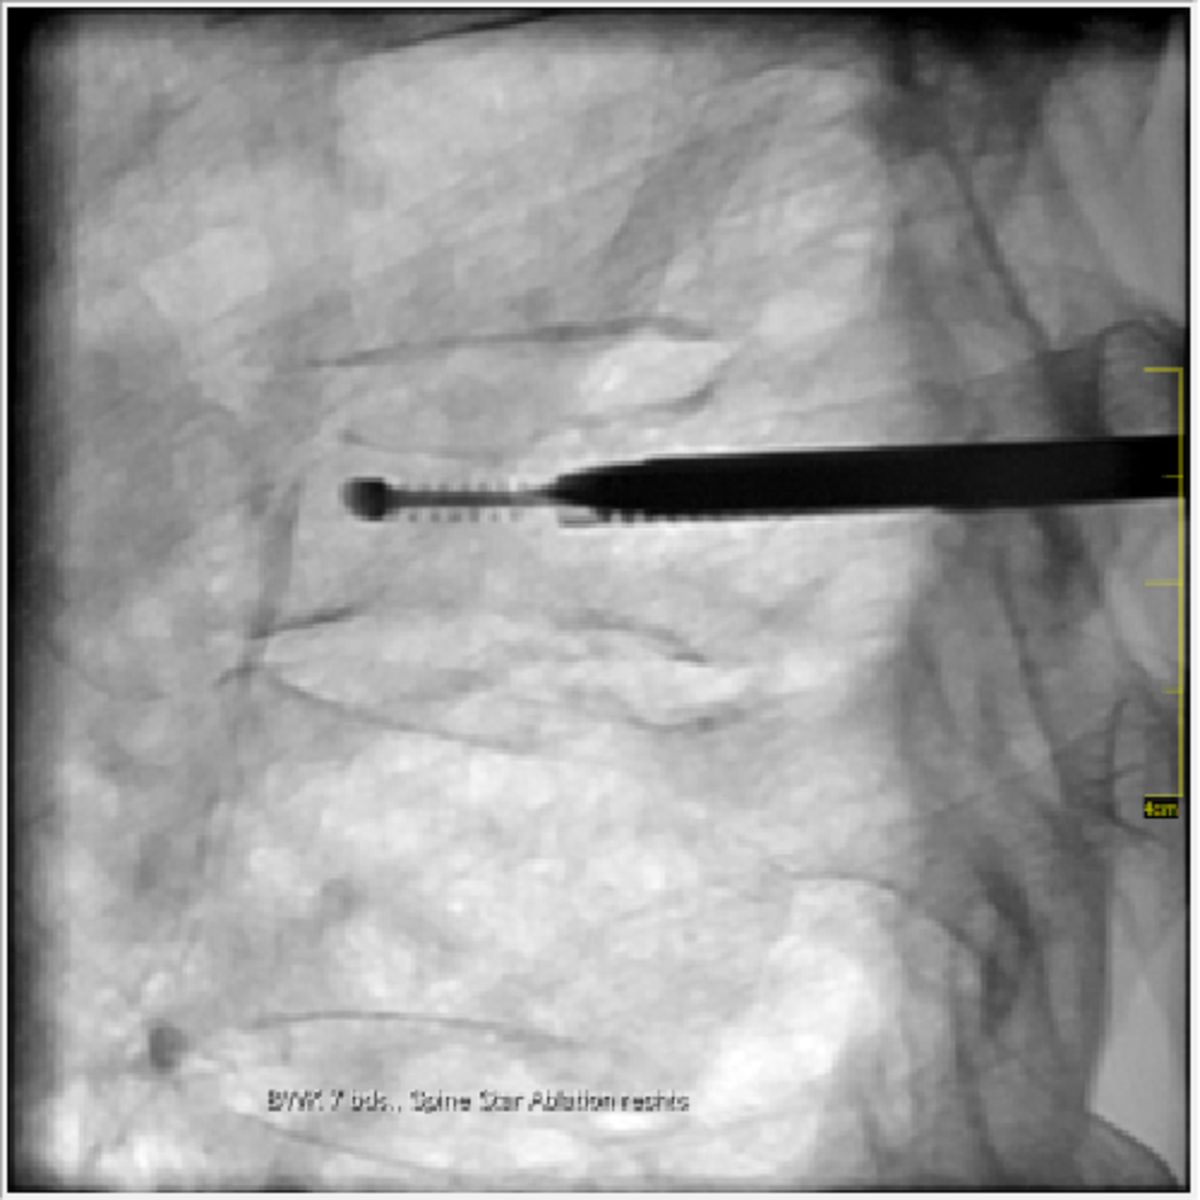

Zur Therapie stehen unsere modernen Großgeräte wie Computertomographen und Durchleuchtungsgeräte (Zwei-Ebenen-Angiographie) zur Verfügung, die schonendes und präzises Arbeiten im Millimeterbereich gewährleisten, was der Sicherheit und der Verbesserung der klinischen Ergebnisse für unsere PatientInnen dient.

- Tumorablation

- Durchleuchtungsgesteuerte Schmerztherapien